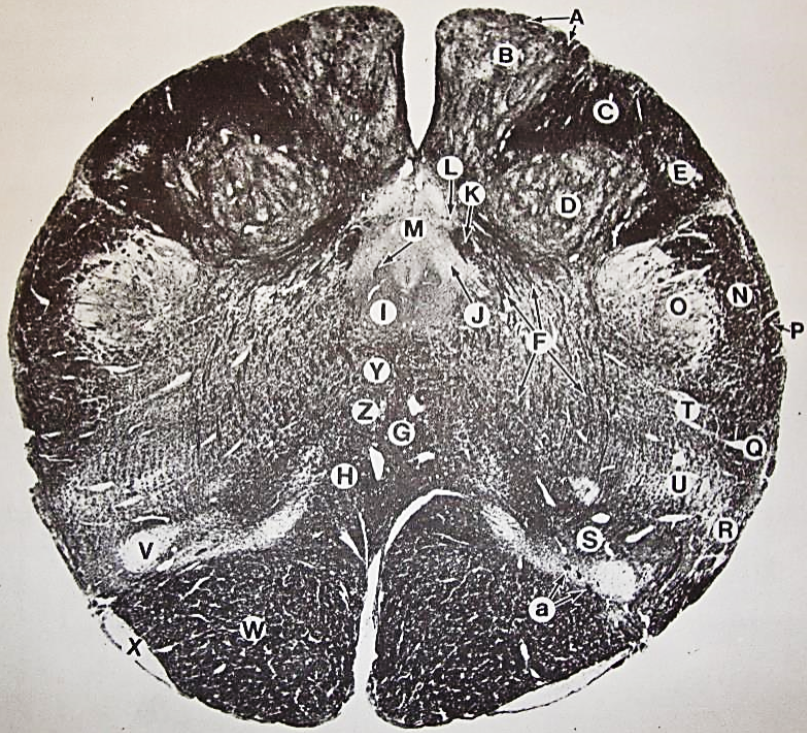

A

Lateral Cuneate nucleus

B

dorsal external arcuate fibers

C + D collectively

vestibular nuclei

C + D collectively

vestibular nuclei

E

dorsal motor nucleus of vagus nerve

F

solitary fasciculus

G

solitary nucleus

H

nucleus ambiguous

I

fascicles of glossopharyngeal nerve

J

hypoglossal nucleus

K

fascicles of hypoglossal nerve

L

dorsal longitudinal fasciculus

M

central tegmental tract

N

inferior olivary nucleus

R

inferior cerebellar peduncle

S

spinal trigeminal tract

T

spinal trigeminal nucleus

U

ventral trigeminothalamic tract

V

pyramidal (corticospinal) tract

W

rubrospinal tract

X

anterior spinocerebellar tract

Y

spinal lemniscus

Z

medial longitudinal fasciculus

a

tectospinal tract

b

medial lemniscus

c

vagus nerve

d

inferior salivatory nucleus